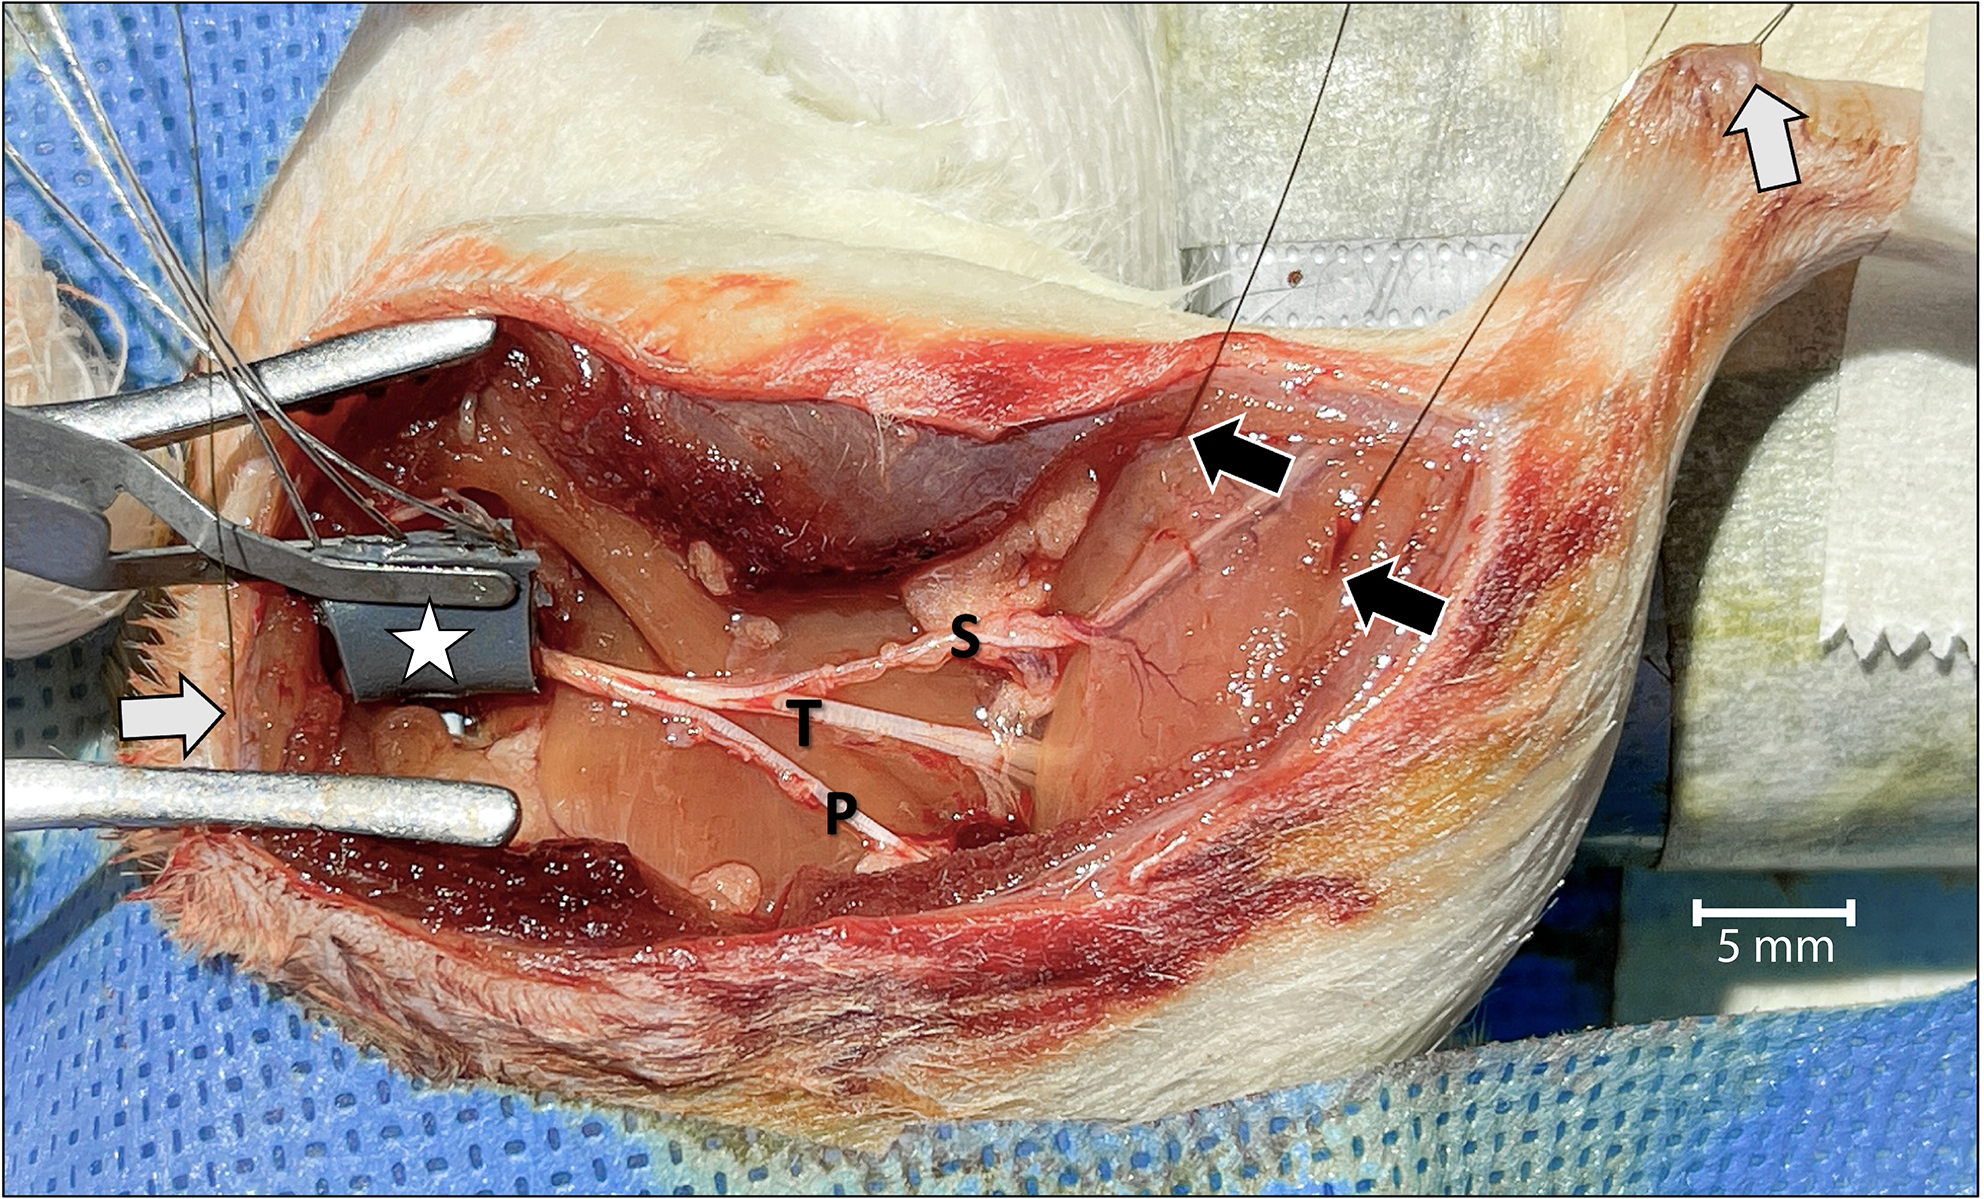

Continuous two-channel CMAP recordings were obtained by placing wire-hook bipolar electrodes (EMG Hook Electrodes, Model EMT-2-30: Microprobes, Inc.; Gaithersburg, MD, United States) at four different locations (Figure 1). One recording electrode each was placed at the muscle belly of the lateral and medial heads of the gastrocnemius, and two corresponding electrodes were placed in the Achilles tendon. A ground electrode was placed under the skin of the back of the rat. A bipolar stimulating cuff electrode was placed around the sciatic nerve proximal to the level of the trifurcation in order to complete the circuit.

Surgical view of the left leg showing the acute dissection and the methods used to establish two-channel CMAP recording and nerve stimulation. Wire-hook recording electrodes were inserted into the belly of the lateral and medial gastrocnemius muscles (black arrows) and Achilles tendon (white arrow in the upper right). A grounding electrode was placed under the skin of the back of the rat (white arrow on the left). The bipolar stimulating nerve cuff electrode with its connecting wires was wrapped around the proximal sciatic nerve at the level of the sciatic notch (star). To isolate motor unit activation corresponding only to the tibial (T) nerve, and to prevent signal interference, the sural (S) and peroneal (P) nerves were cut. The tibial nerve was crushed just distal to the point of sural nerve take-off. For orientation, the rostral direction is down to the left.